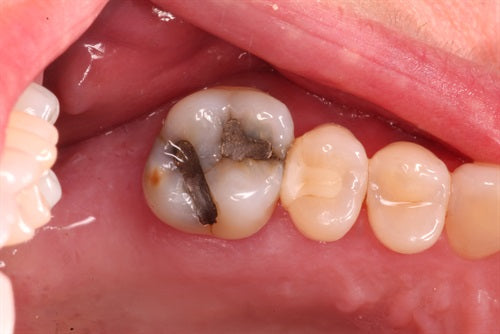

#16 Large composite by Dr. Ahmad Fayad

The below case was completed and documented by our guest presenter, Dr. Ahmad Fayad. This is a great example of a Greater Curve band and technique at work! Introduction: In... Read More